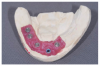

A patient with inadequate maxillary bone

for implants.

Figure 1

An upper denture ridge with

minimum topography.

Figure 2

An upper denture

ridge with good morphology.

Figure 3

Many patients have been edentulous in both arches for long periods of time with extensive bone loss. Some have very little remaining maxillary bone and a mandibular arch that can receive implants only in the region anterior to the mental foramina (Figure 1 through Figure 3). Removable prosthetic devices, especially those not supported by teeth, offer varying levels of stability in function. Several factors must be considered when designing the occlusal scheme for combinations of completely removable, tooth-supported removable, and implant-supported fixed prosthetics. Air pressure; surface area; peripheral seal residual ridge form and morphology; resistance and retention elements; fulcrum mechanics; and dislodging features require assessment and integration to create a satisfactory prosthetic solution for each patient’s situation.